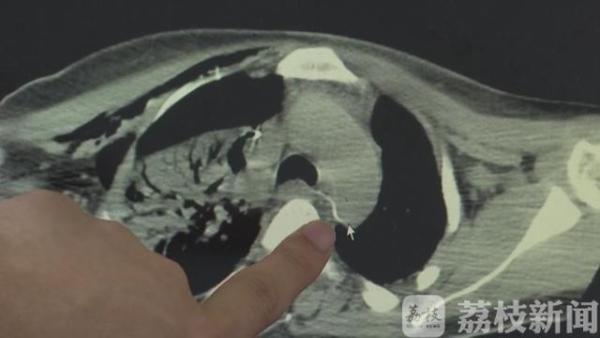

常州二院胸心外科主任童继春:“这里跟主动脉关系很厉害,跳动就会走,这是术中拍的。”

常州市二院胸心外科、消化内科、麻醉科等多学科合作紧急会诊后,决定在胸腔镜下,由内镜取出鱼刺。然而在内镜探查过程中,食管、胃里均找不到鱼刺,医生随即采取术中定位,发现鱼刺已经刺穿食管,转移到食道边缘处,一旦戳破主动脉便会导致大出血,从而危及生命。